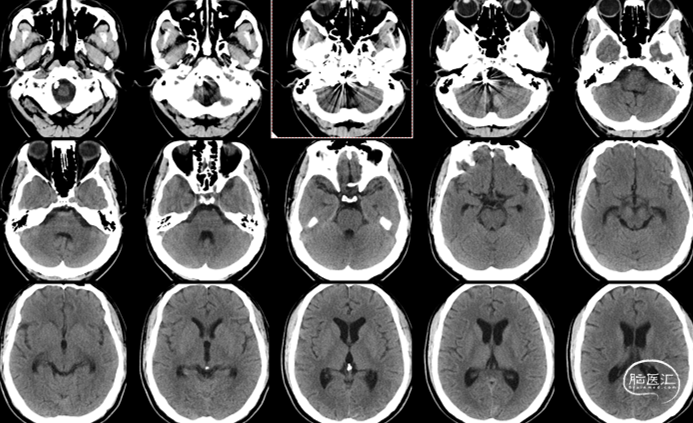

CTA:

右侧椎动脉(优势侧)V4段梭形动脉瘤,

左侧椎动脉纤细,后交通动脉未显影。

影像科提供的重建图像就像美颜照片,虽然好看,但丢失了诸多细节。

我们使用影像工作站重建的图像能够看到更多细节:

动脉瘤处有明显的凹陷,考虑为动脉夹层的内膜瓣;动脉瘤累及小脑后下动脉(PICA)的开口。

3D造影:动脉瘤处有明显的凹陷,符合夹层内膜瓣表现;PICA从动脉瘤远端发出,动脉瘤大小约6.5×12.8mm,受累椎动脉直径约4.3mm,覆盖远近端达正常血管约需30mm支架长度。